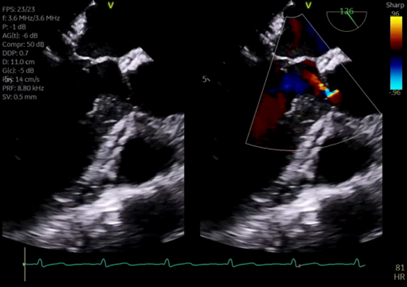

Image 7

7. What is the significance of the bright vertical lines visualized on either side of the continuous wave doppler profile?

This image shows a continuous wave doppler (CWD) profile of blood flow across the aortic valve.  The flow is depicted as a negative deflection on the Y axis because the flow is travelling away from the TEE probe resulting in a negative doppler shift.  Each peak is a visualization of instantaneous velocities of blood flow over time, in this case across the aortic valve. A typical CWD profile does not include the bright vertical lines visualized at both the beginning and end of systole in each cardiac cycle in image 7.  These lines are an artifact created by the opening and closing of this patient’s new mechanical aortic valve, and are pathognomonic for the presence of a mechanical prosthesis.